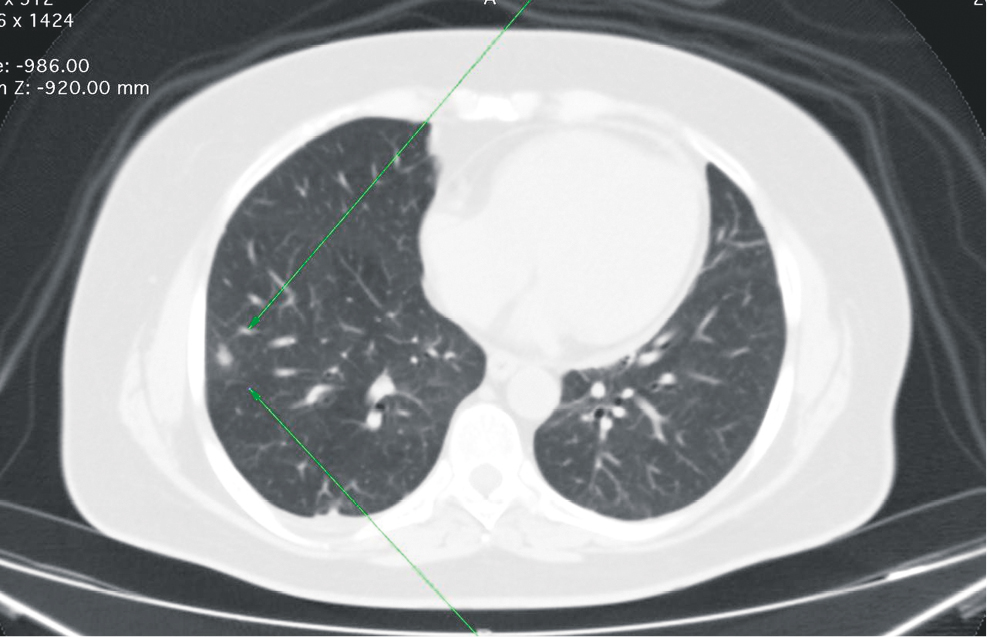

Методика маркировки периферических новообразований легких посредством предоперационной установки системы «якорной метки»1. Непосредственно перед оперативным вмешательством пациентам выполнялась визуализация патологического участка легкого по описанной выше методике (рис. 3) с последующей трансторакальной установкой системы «якорной метки» под местной анестезией 20 мл 0,5 % раствора лидокаина (рис. 4, 5).

Рис. 4. Компьютерная томограмма груди в аксиальном срезе, пациент И., 44 года. Установка системы «якорной метки» в легочную паренхиму в зону новообразования (зеленые стрелки)

Fig. 4. Axial computed tomography scan of the chest, Patient I, 44 years old. Placement of an anchor marker system into the lung parenchyma in the area of the neoplasm (green arrows)